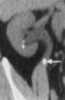

Kidney stone

Kidney stone disease, also known as nephrolithiasis or urolithiasis, is when a solid piece of material (kidney stone) develops in the urinary tract. Kidney stones typically form in the kidney and leave the body in the urine stream. [Source: Wikipedia ]